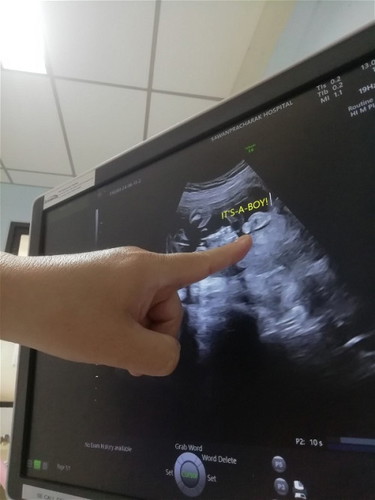

ตอนนี้ตั้งครรภ์ได้24week5day แล้วค่ะ เท่ากับกี่เดือนคะ... แล้วแม่ๆซื้อของเตรียมคลอดกันตอนไหนคะ....

ท้อง3แล้วค่ะ...ได้ผู้ชายค่ะ